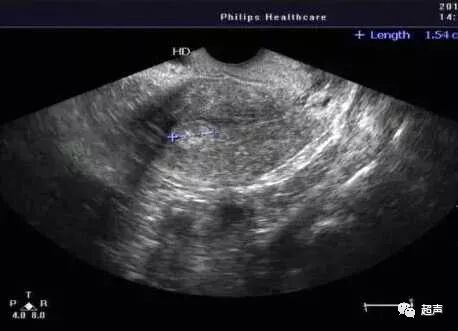

宫腔分离